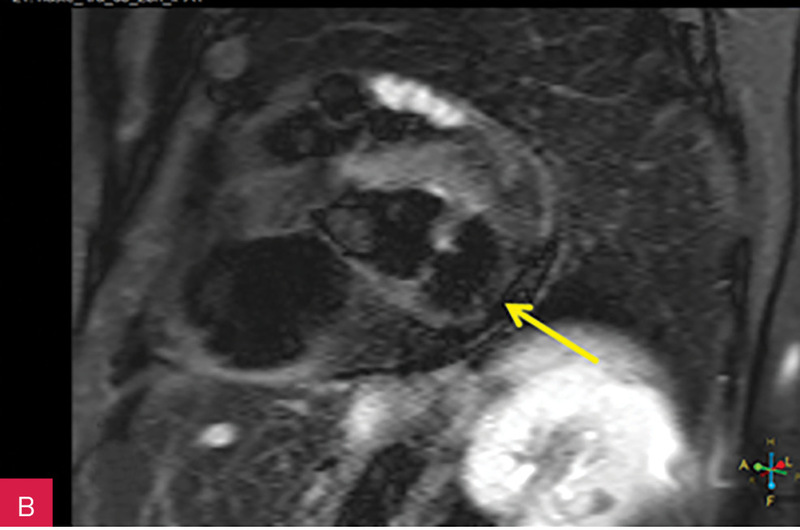

Rycina 7A-D. Obrazy rezonansu magnetycznego w osi krótkiej na wysokości pierścienia mitralnego: czarnej krwi T1-zależne TSE (A); czarnej krwi T2-zależne HASTE (B); T1-zależne echa gradientowego dynamicznie podczas podawania środka kontrastowego (C); sekwencja SSFP, pojedynczy obraz w osi krótkiej (D). W dolno-bocznej części pierścienia mitralnego od strony światła lewej komory zmiana (strzałki) niskosygnałowa we wszystkich ważeniach sygnału

Rycina 8A, B. Obrazy rezonansu magnetycznego w projekcji pięciojamowej (A) i dwujamowej (B) z późnym wzmocnieniem kontrastowym – widoczna zmiana ulegająca brzeżnemu wzmocnieniu kontrastowemu. Całość obrazu wskazuje na serowate zwapnienie pierścienia mitralnego (CCMA)

W celu weryfikacji zmiany i oceny charakterystyki tkanki wykonano CMR,

w którym stwierdzono w dolno-bocznej części pierścienia mitralnego od strony światła lewej komory zmianę odpowiadającą morfologicznie CCMA, obejmującą 7,3 cm obwodu pierścienia mitralnego, o grubości w osi krótkiej do 25 mm, w osi długiej do 21 mm; zmiana ulegała brzeżnemu wzmocnieniu kontrastowemu i powodowała ograniczenie ruchomości tylnego płatka zastawki mitralnej, obejmowała struny ścięgniste mięśnia brodawkowatego tylno-przyśrodkowego. Ponadto uwidoczniono znacznie powiększone przedsionki z istotnym włóknieniem – jak w restrykcji (ryc. 7, 8).